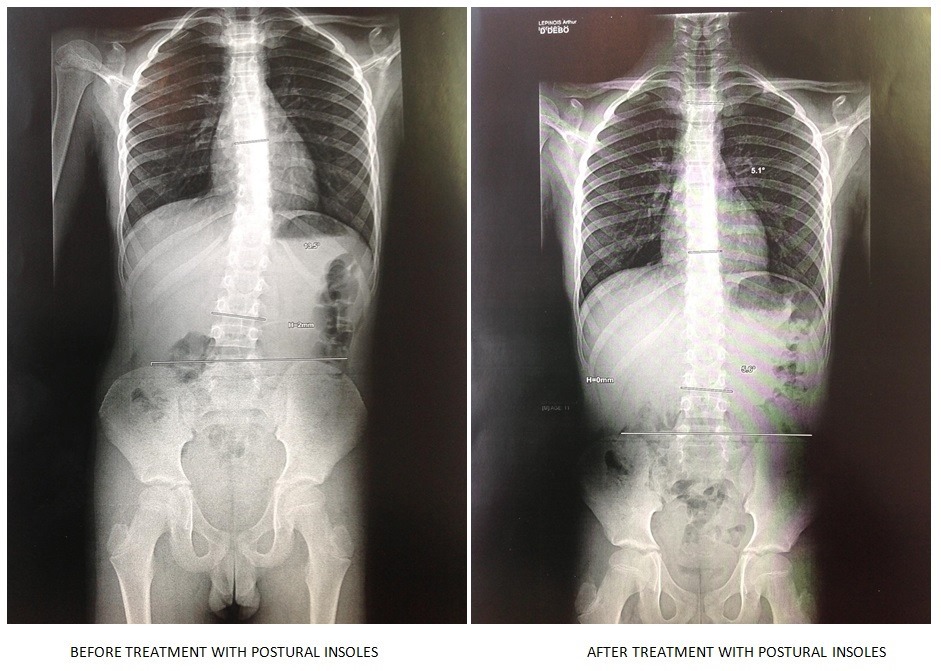

Our services include detailed posture assessments, custom foot care solutions, manual osteopathic treatments, and personalized rehabilitation programs.

-Posturologie-Podologie